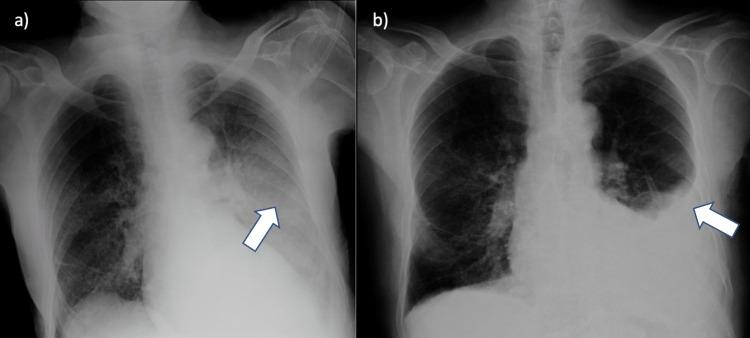

Eosinophilic granulomatosis with polyangiitis (EGPA) is a rare form of systemic disease characterized by inflammation and necrotizing effects of the small and medium blood vessels. It is a vasculitis found in all age groups and both genders, although its etiology is unknown. The mean age at diagnosis is 40 years, consisting of an uncommon cause of vasculitis in people older than 65 years. It is the least common of the three antineutrophil cytoplasmic antibody (ANCA)-associated vasculitis (EGPA, granulomatosis with polyangiitis (GPA), and microscopic polyangiitis). The characteristic features of EGPA include extravascular eosinophilic granulomas, peripheral eosinophilia, and asthma, usually responsive to steroid treatment. In this article, we discuss a case of an 83-year-old male with a history of undetermined etiology of chronic kidney disease, chronic obstructive pulmonary disease (COPD), and severe chronic rhinosinusitis with nasal polyposis. First hospitalized with the suspicion of community-acquired pneumonia (CAP), based on worsening blood eosinophilia and unresolving respiratory symptoms, a suspicion for EGPA was raised. The development of an eosinophilic pleural effusion, later upon admission, was a predominant factor for its confirmation, as it constitutes a rare finding, only present in about 30% of patients. Laboratory tests showed elevated IgE, the presence of antineutrophil cytoplasmic antibodies directed against myeloperoxidase with a perinuclear staining pattern (ANCA-MPO), and the absence of antiproteinase 3 (anti-PR3) ANCA, which were consistent with the diagnosis. A pleural biopsy was then made, revealing fibrosis with the presence of eosinophils, although with no evidence of granulomas. According to the most recent and accepted classification criteria, the "2022 American College of Rheumatology and European Alliance of Associations for Rheumatology (ACR/EULAR) for EGPA," this patient presented with a score of 13 (a score greater than or equal to 6 is needed for the classification of EGPA). Hence, a diagnosis of EGPA was assumed, and the patient was initiated on corticosteroid therapy, with a favorable response. The aim of this article is to present a rare case of EGPA diagnosis made at the age of 83 years old, although there was evidence that could point to this disease years before the diagnosis was made. In the present case, it is important to point out the long diagnostic delay in a geriatric patient, much older than the median age of diagnosis for EGPA, culminating in a curious case of uncommon pleuroparenchymal involvement.